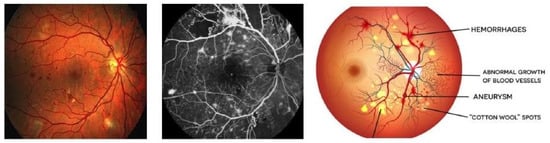

The success of DL models in predicting DR depends on the availability of high-quality and diverse datasets. These datasets typically consist of thousands of annotated retinal images, allowing the model to learn and generalize the patterns associated with different stages of DR. Our dataset comprises retinal scan images subjected to Gaussian filtering for diabetic retinopathy detection. These images, sourced from the APTOS 2019 Blindness Detection dataset [34], were resized to 224 × 224 pixels to facilitate compatibility with various pre-trained deep learning models. The dataset is organized based on the severity or stage of DR, as outlined in the accompanying train.csv file [34]. There are five distinct directories representing different severity levels, as follows: 0—no DR, 1—mild, 2—moderate, 3—severe, and 4—proliferative DR. This categorization enables a stratified analysis, aiding in the development and evaluation of predictive models for DR at various stages. Regarding the number of images categorized by DR levels, there were 1805 images in the “no DR” class, indicating the absence of DR. Mild DR was represented by 370 images. Figure 1 shows a sample image from original data file [34], image has been shown in two separate color to identify some retinal lesions clearly.

Figure 1. Images showing distinct DR in a human eye. Moderate DR has 999 images. The severe DR class consists of 193 images, and the proliferative DR class comprises 295 images. These counts offer a comprehensive overview of the distribution of images across different DR levels in the dataset.